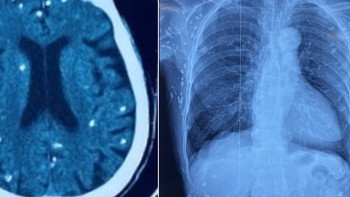

02/12/2025 08:42Rùng mình với hình ảnh nang sán dây lợn gây vôi hóa đầy cơ thể

Mặc dù không phát hiện ký sinh trùng sán dây lợn tại thời điểm bệnh nhân nhập viện, nhưng các bác sĩ phát hiện nhiều tổn thương ở não, dưới da vùng bụng ngực, ngực do nang sán dây lợn vôi hóa.